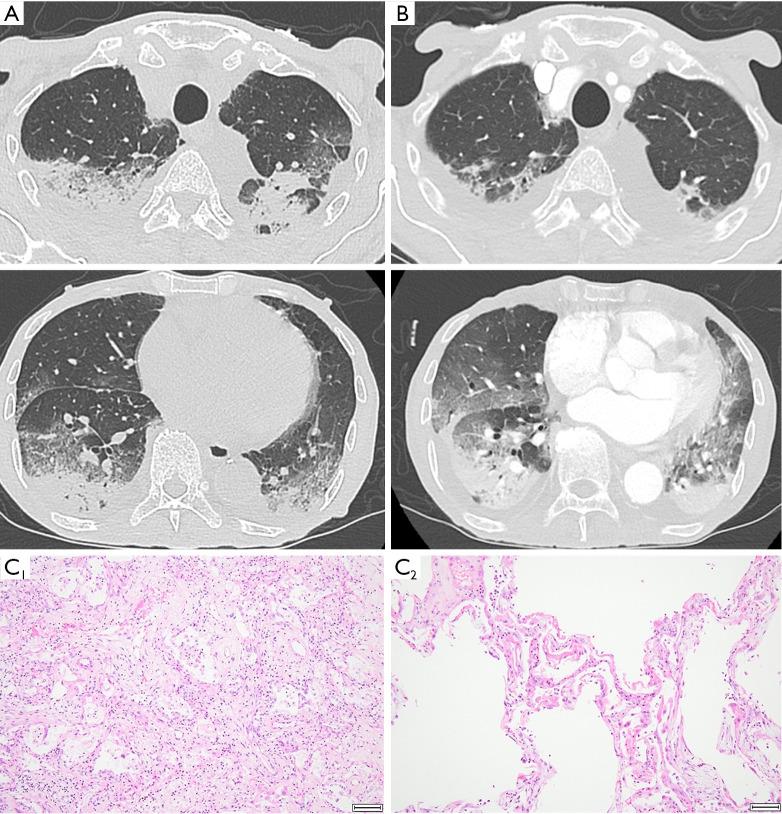

The two patients were in their 70s, male and diagnosed gastric cancer with peritoneal dissemination. The patient of case 1 underwent surgery and adjuvant chemotherapy nine years before. The patient of case 2 was diagnosed unresectable 6 months before and chemo naïve. Both patients received nivolumab plus S-1 and oxaliplatin for the dissemination. The onset of both cases occurred after the fifth dose of the regimen, and the responses to corticosteroids were transient and limited. Computed tomography showed bilateral consolidation and ground-glass opacities, seemingly similar to an organizing pneumonia pattern. Acute and organizing stages of diffuse alveolar damage were detected histopathologically. Despite showing notable antitumor effects, both patients had indications of interstitial pneumonitis before admission, such as elevation of C-reactive protein (CRP) and Krebs von den Lungen-6 (KL-6) levels and slight lung opacity or respiratory symptoms approximately 10 days before admission.

这两名患者均为70多岁男性,被诊断为伴有腹膜播散的胃癌。病例1的患者9年前接受了手术及辅助化疗。病例2的患者6个月前被诊断为不可切除且未接受过化疗。两名患者均因播散接受了纳武利尤单抗加S - 1和奥沙利铂治疗。两例病例均在该方案第五次给药后发病,对皮质类固醇的反应短暂且有限。计算机断层扫描显示双侧实变和磨玻璃影,看似类似于机化性肺炎模式。组织病理学检查发现了弥漫性肺泡损伤的急性和机化阶段。尽管显示出显著的抗肿瘤效果,但两名患者在入院前均有间质性肺炎的迹象,如入院前约10天C反应蛋白(CRP)和胃泌素释放肽前体(ProGRP)水平升高以及轻微的肺部模糊影或呼吸道症状。